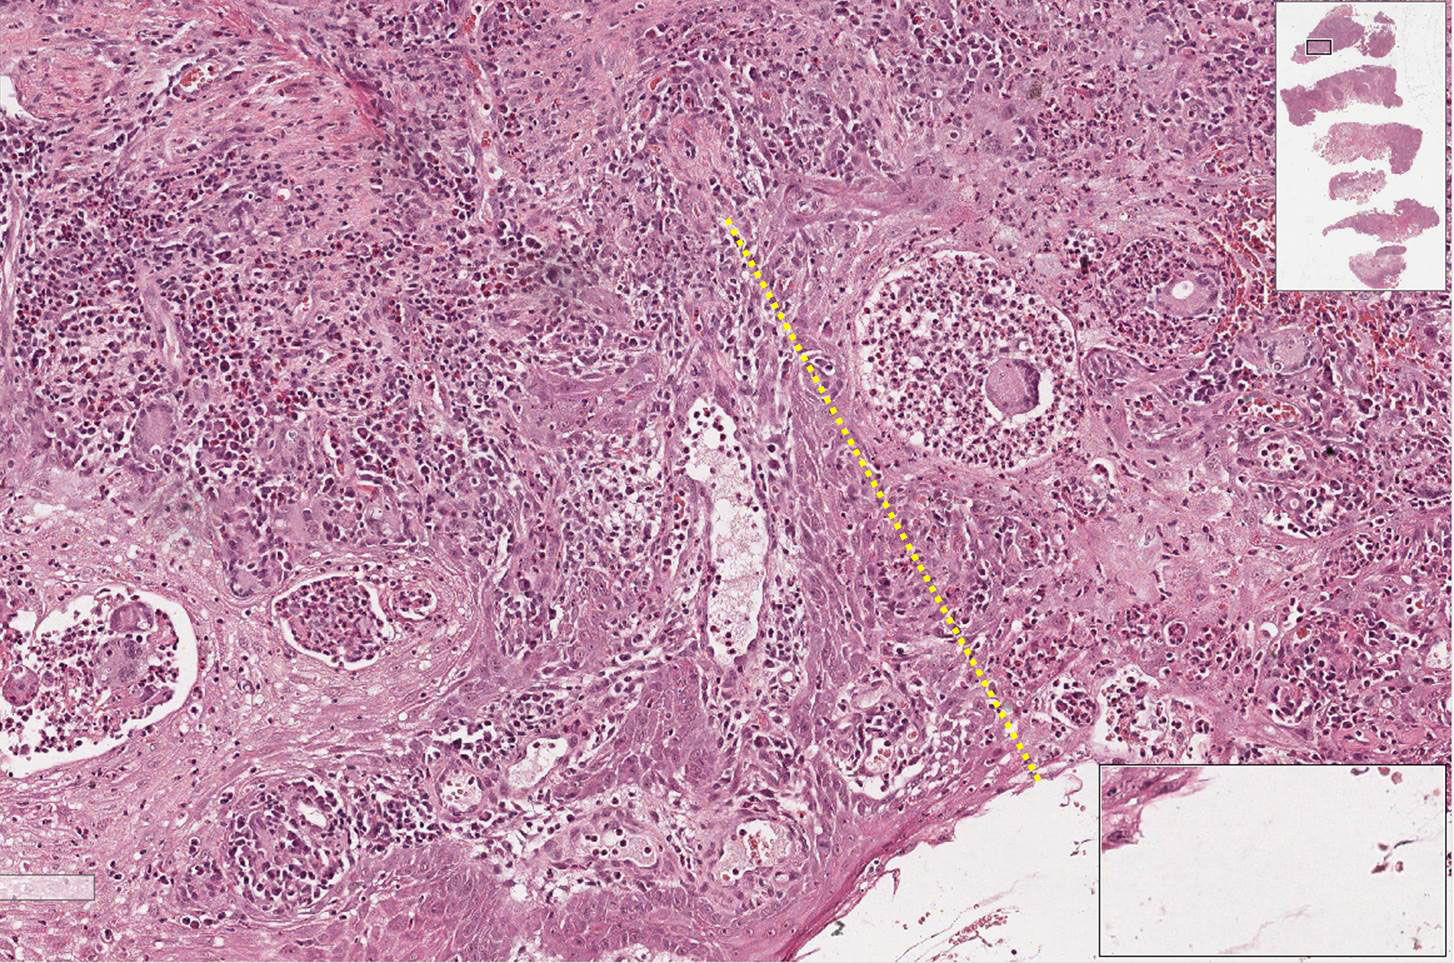

Fragmento de mucosa revestido por tecido epitelial estratificado pavimentoso paraceratinizado, apresentando hiperplasia pseudoepiteliomatosa (sensação de que o epitélio “invade” o tecido conjuntivo) e áreas de micro abcessos (pequenas coleções de neutrófilos e piócitos superficiais). No tecido conjuntivo subjacente, observa-se a formação de granulomas que apresentam externamente fibroplasia, seguida por um colar de linfócitos, e mais centralmente observam-se um aglomerado de macrófagos epitelióides (núcleo claro e alongado e as células podem apresentar um arranjo em paliçada ou justapostas umas às outras). Entremeados as células do granuloma observam-se células gigantes do tipo Langhans. Em algumas áreas, principalmente no interior das células gigantes, é possível visualizar os fungos que se apresentam como um espaço negativo (branco) e forma geométrica redonda.

Observar os granulomas compostos por um aglomerado de macrófagos epitelióides, colar de linfócitos e fibroplasia externa assim como a presença de células gigantes fagocitando os fungos. Os microabscessos e a hiperplasia pseudoepiteliomatosa são sugestivos, mas não específicos desta doença.